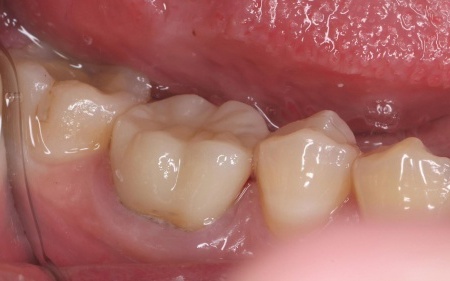

30代女性 破折した古い被せ物を除去してジルコニアクラウンで修復した症例

拝見したところ、右下奥歯に装着されていた被せ物が、経年劣化による強度の低下で大きく破折していました。

まずは右下奥歯の古い被せ物を除去し、歯の形を丁寧に整えます。

続いて精密な型取りを行い、周囲の歯と色調や形を合わせたジルコニアの被せ物を作製しました。

後日、完成した被せ物を装着し、見た目や噛み合わせに問題がないことを確認して、治療を終了しています。